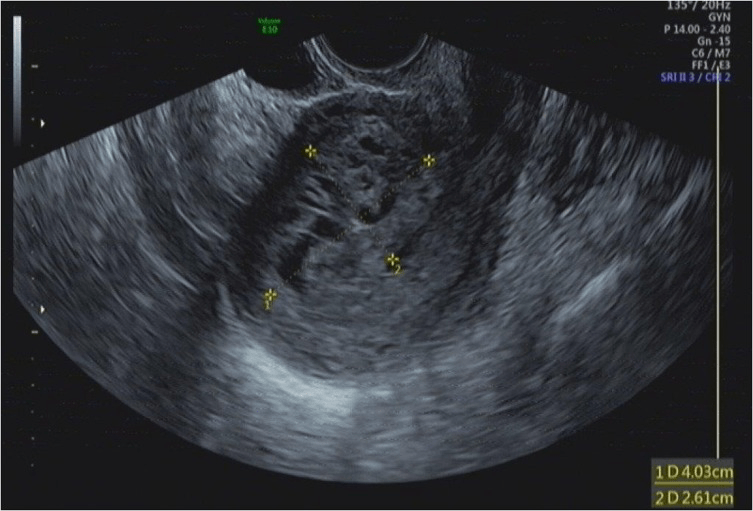

Pelvic Ultrasound

- Identify ongoing pregnancy

- Duration and site of pregnancy

- Adnexal mass

- Free fluid

- Echogenic material in the uterus or a thickened stripe commonly seen after a medical or surgical abortion and should not immediately trigger further intervention

May demonstrate:

- Retained products of conception

- Free fluid in the abdomen (suggests uterine perforation)

- Hematometra (accumulation of blood in the uterus)